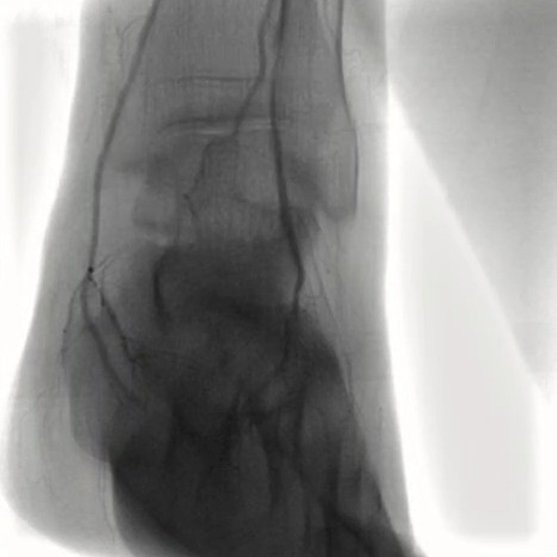

MRI/CT interpretation and Thrombectomy and stenting/ plasty for acute and recurrent stroke. Cerebral DSA

Opening narrowed arteries to restore healthy blood flow.

Acute ischemic limb ALI and critical limb ischemia CLI treatment by thrombectomy.

Outcomes observed in patients treated with image-guided, minimally invasive vascular procedures.

Results vary by patient and condition. Images are for educational purposes only.